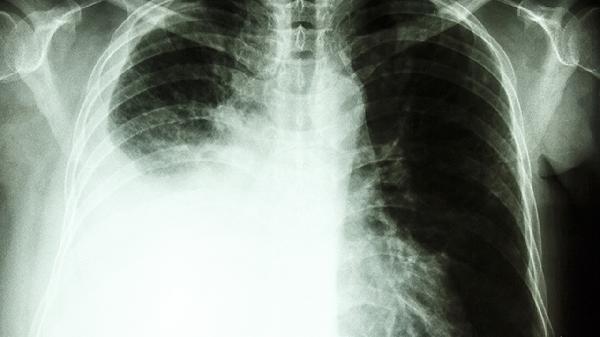

鼻咽癌的治療需結(jié)合放療、化療、手術(shù)及中醫(yī)藥綜合干預(yù),早期發(fā)現(xiàn)可顯著提高生存率。

鼻咽癌對放射線敏感,調(diào)強(qiáng)適形放療IMRT能精準(zhǔn)靶向腫瘤組織,減少周圍正常組織損傷。對于局部晚期患者,同步放化療可提升療效,5年生存率可達(dá)60%-80%。放療期間配合滋陰清熱中藥如沙參麥冬湯,可緩解口干咽痛等副作用。